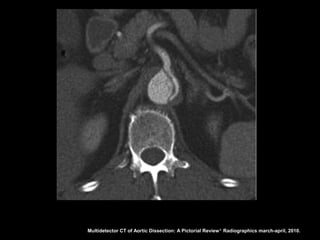

Dissecção aórtica

Stanford B

O flap intimal localiza-se após a emergência da

artéria subclávia esquerda;

É importante localizar os sítios de laceração porque

a cirurgia e os procedimentos de colocação de

prótese objetivam a oclusão das lacerações para

induzir a formação de trombo na luz falsa;

Multidetector CT of Aortic Dissection: A Pictorial Review 1. Radiographics march-april, 2010.